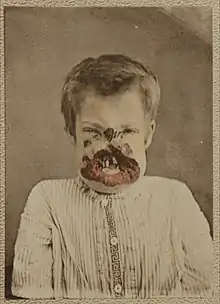

Untreated early syphilis infections results in a high risk of poor pregnancy outcomes, including saddle nose, lower extremity abnormalities, miscarriages, premature births, stillbirths, or death in newborns. Some infants with congenital syphilis have symptoms at birth, but many develop symptoms later. Symptoms may include rash, fever, large liver and spleen, and skeletal abnormalities.[16] Newborns will typically not develop a primary syphilitic chancre but may present with signs of secondary syphilis (i.e. generalized body rash). Often these babies will develop syphilitic rhinitis ("snuffles"), the mucus from which is laden with the T. pallidum bacterium, and therefore highly infectious. If a baby with congenital syphilis is not treated early, damage to the bones, teeth, eyes, ears, and brain can occur.[16]

- Saddle nose (collapse of the bony part of nose)

- Rhagades, linear scars at the angles of the mouth and nose result from bacterial infection of skin lesions